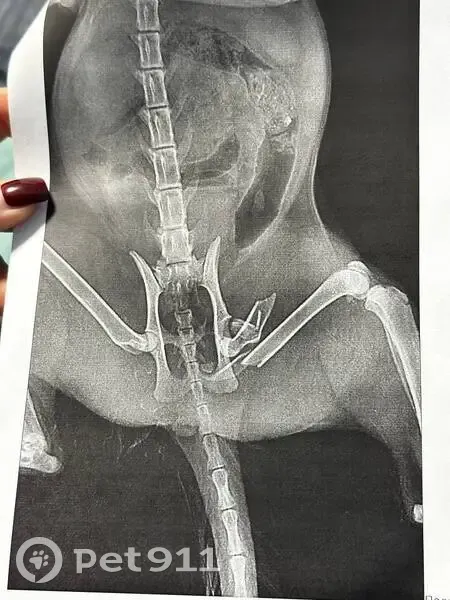

Найдена кошка в Перми, район Садового (02.11.2025). Молодая, примерно 2-3 года, небольшая по размеру. Серо-белая, ухоженная, чистая, воспитанная, явно домашняя. Была сломана лапа и шейка бедра, есть сильные ушибы мягких тканей живота (возможно, падение с высоты) по этому матка не визуализируется - неизвестно, стерилизована ли. Также есть следы укусов собак. Точно сказать, что произошло, сложно. Если кто-то потерял кошку в этом районе - отзовитесь, пожалуйста.